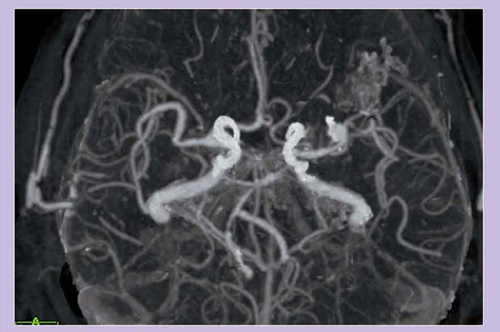

図7 aのコンベンショナルCTAのMIP画像では,かなり強い石灰化が認められるが,bのDEイメージング骨除去画像では石灰化がきれいに抜けていて,cのDSAとほぼ同様な画像が得られ,狭窄率を正確に計測可能である。

石灰化のある13症例(18断面)の狭窄率について,骨除去CTAとDSAを比較した結果,非常に良い相関を示す結果が出ている。

図7 頸部血管狭窄

a:コンベンショナルCTA

b:DE骨除去CTA

c:DSA